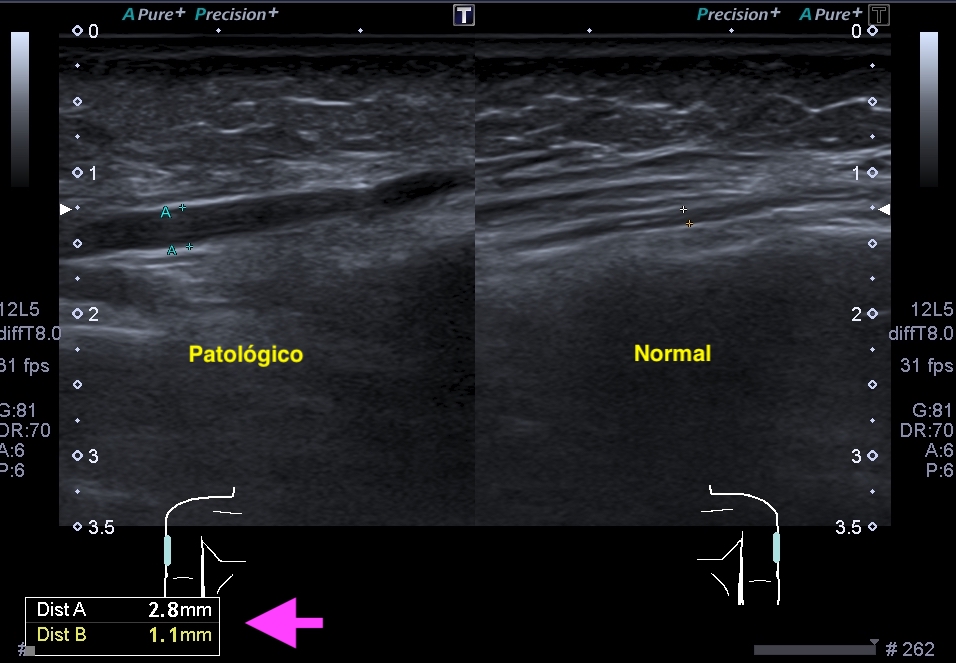

En la mayoría de los casos que el paciente comenta dolor en la parte postero lateral del brazo en el tercio medio la exploración ecográfica es normal, pero ojo si encontramos estas imágenes que vas a ver a continuación, debemos comentarlas y documentarlas ya que hablan por si mismas:

Semiológicamente el patrón normal de un nervio tiene aspecto de un cable que cortamos por la mitad y vemos como sus hilos conductores están seccionados en eje corto y alargados en eje largo. Su aspecto es ligeramente hiperecogénico. Cuando pierde su ecoarquitectura normal se vuelve hipoecogénico y aumenta su grosor, exactamente igual que tienes en la imágenes que has podido estudiar previamente.